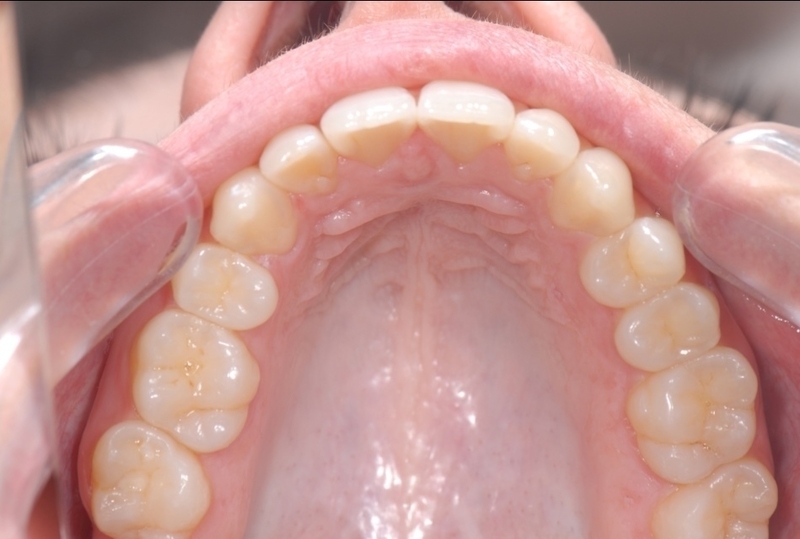

Cas clinique

Cas 1 - Orthodontie par aligneurs invisibles

Après